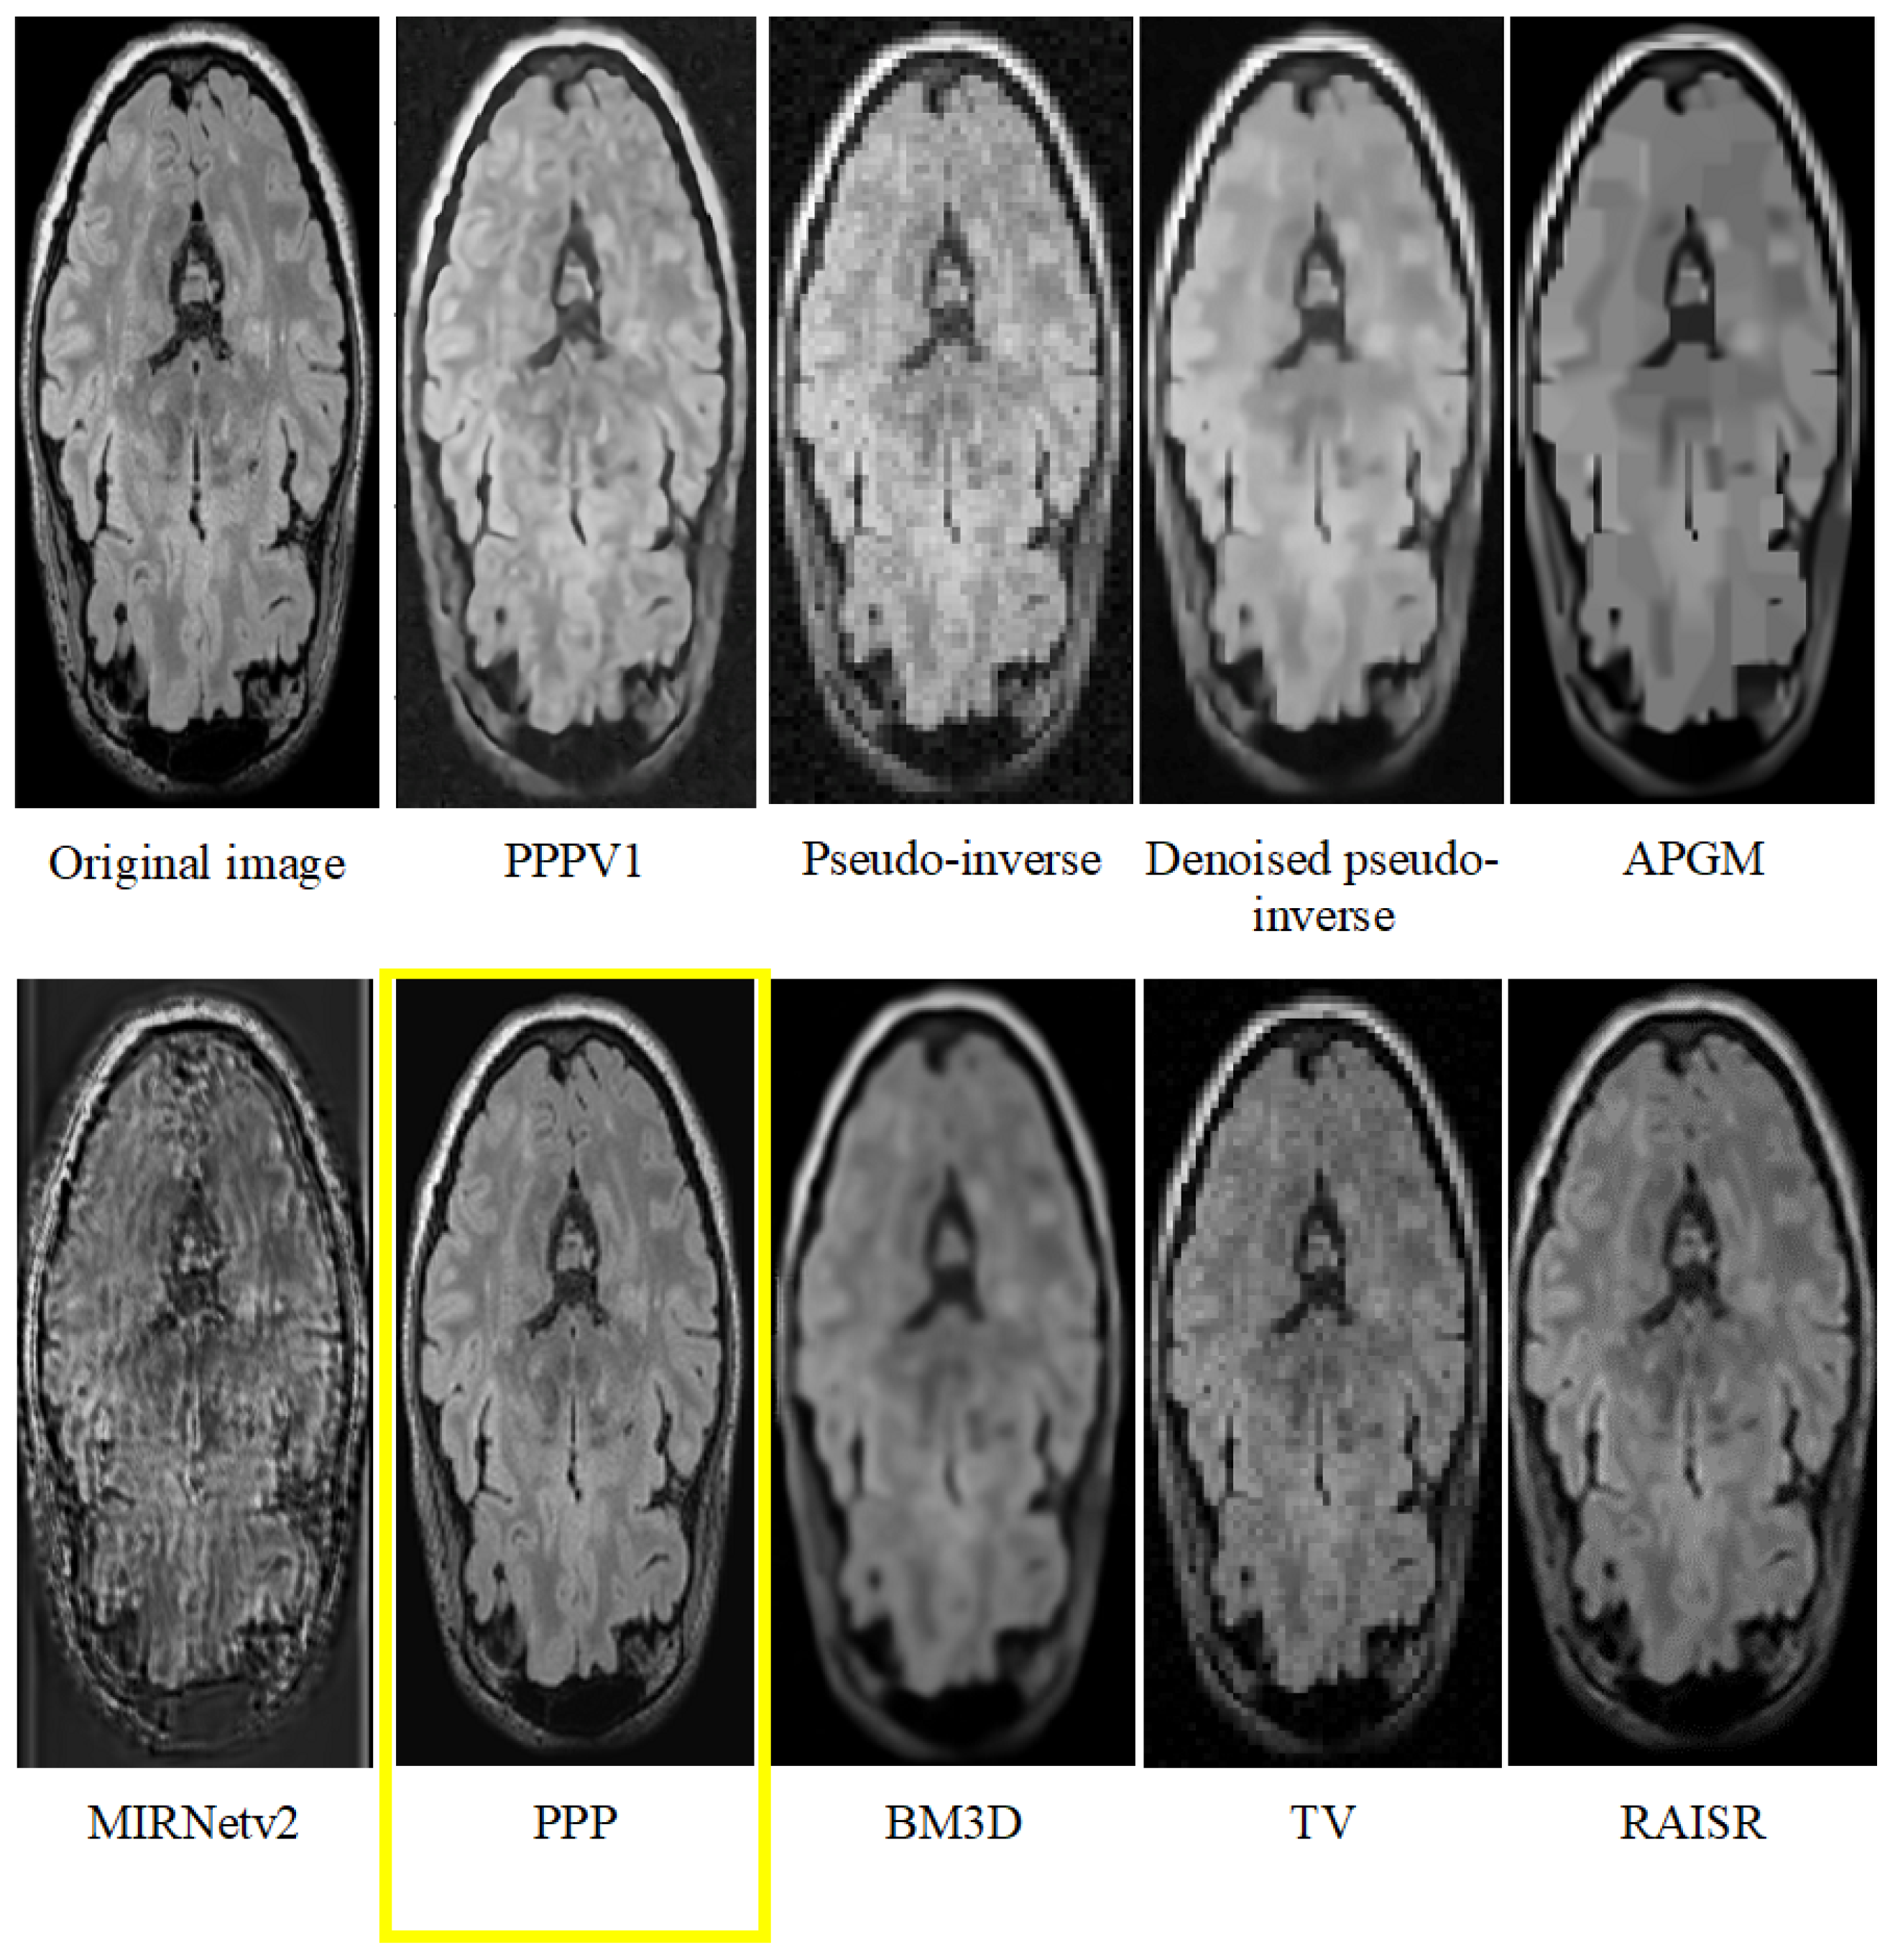

| Dataset 1 | Dataset 2 | |||

|---|---|---|---|---|

| Average | St.Dev | Average | St.Dev | |

| PPPV1 | 22.49 | 0.44 | 25.26 | 0.25 |

| Pseudo-inverse | 19.52 | 0.56 | 22.81 | 0.26 |

| Denoised pseudo-inverse | 20.36 | 0.51 | 23.73 | 0.28 |

| APGM | 19.91 | 0.34 | 23.78 | 0.22 |

| MIRNetv2 | 14.05 | 0.27 | 14.26 | 0.18 |

| PPP | 26.59 | 0.49 | 25.67 | 0.65 |

| BM3D | 20.58 | 0.82 | 23.72 | 0.36 |

| TV | 22.48 | 0.44 | 23.50 | 0.29 |

| RAISR | 21.99 | 0.43 | 25.77 | 0.32 |